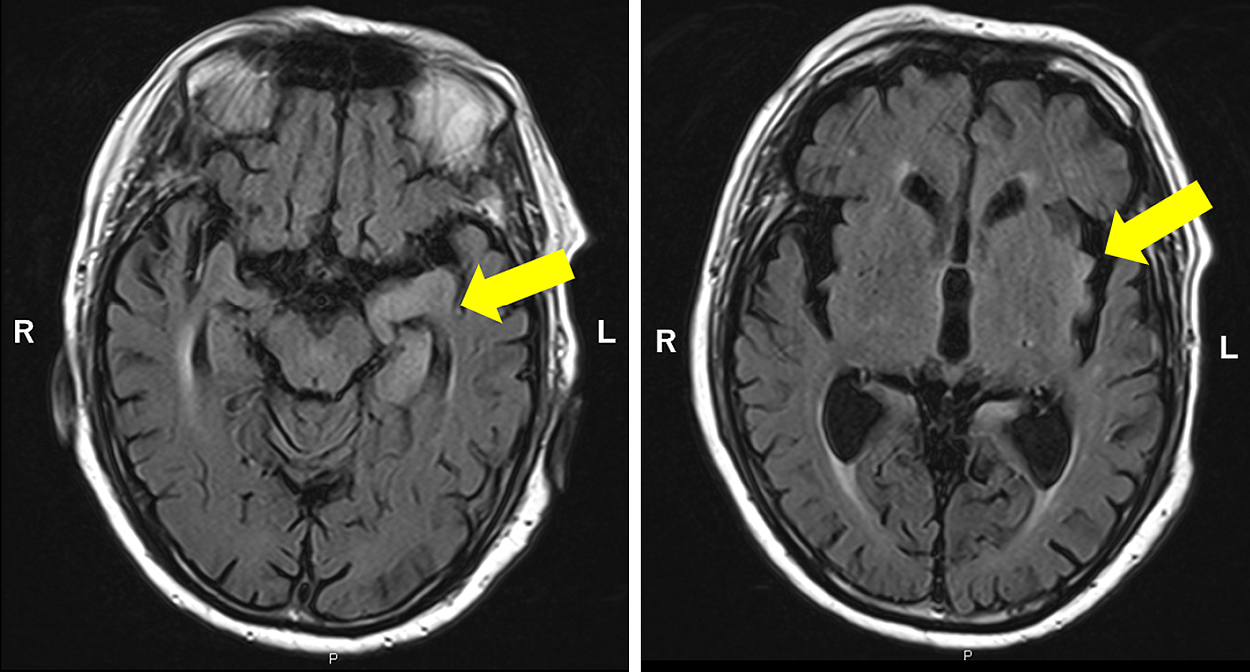

Claustrum signを呈したfebrile infection related epilepsy syndrome(FIRES)の55歳女性例

Febrile infection-related epilepsy syndrome (FIRES) with the claustrum sign in a 55-year-old woman: a case report

赤尾 剛, 市川 大, 藤盛 寿一, 中島 一郎

Go Akao, Dai Ichikawa, Juichi Fujimori, Ichiro Nakashima

2026/03/11